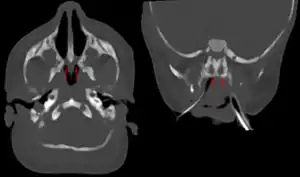

| Bilateral membranous choanal atresia in CT scan | |

Choanal atresia can be suspected if it is impossible to insert a nasal catheter.[5] Also, if one notices a continuous stream of mucus draining from one or both nostrils, it could be a sign of an atresia. Another common sign is cyanosis in an infant while breast feeding, as breathing is dependent on nasal patency in this situation.[5] Diagnosis is confirmed by radiological imaging, usually CT scan.[5] In 1950, in Franklin County, NY, a nurse noticed that a day-old infant turned blue when bottle-fed. “There is something wrong with the baby. We are sending her to Montreal!” The baby was hospitalized over a year. The ENT Surgeon had to gerry-rig a dental drill to accomplish the repair. In 2020, neonatal care for bilateral choanal atresia is much improved.